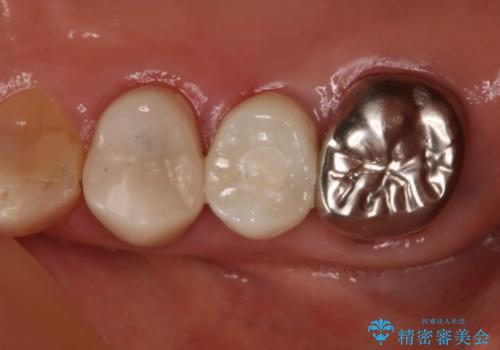

- 右下6番のメタルインレー脱離のため来院。

セラミックの治療を希望されたため切削量を考慮し、セラミックインレーでの治療を選択しました。

う蝕が深くまで進行していたので、CRで裏層した上で形成・印象をしています。